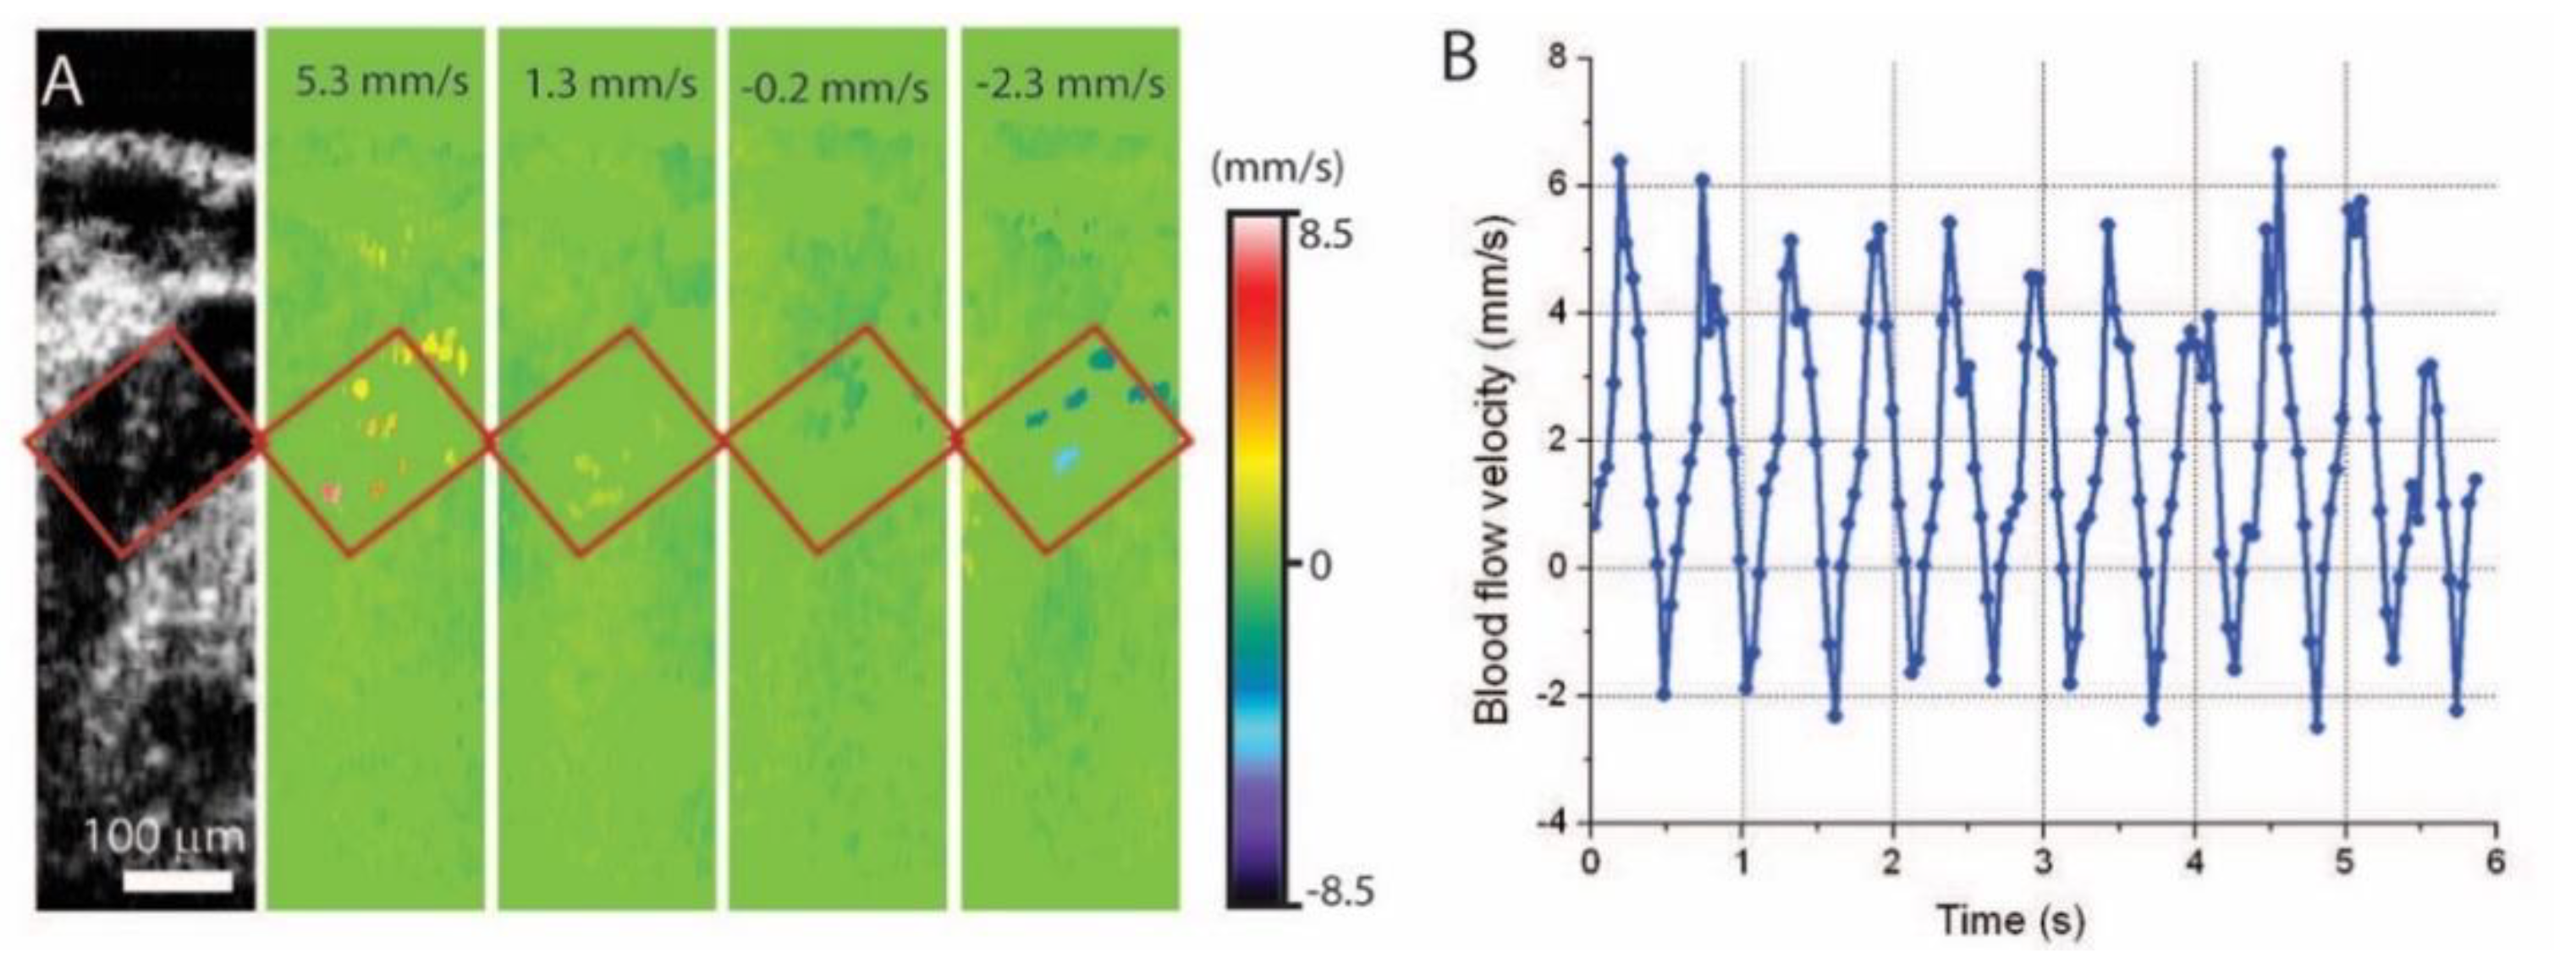

5. Hemodynamic Imaging with Doppler OCT

- Larina, I.V.; Ivers, S.; Syed, S.; Dickinson, M.E.; Larin, K.V. Hemodynamic measurements from individual blood cells in early mammalian embryos with Doppler swept source OCT. Opt. Lett. 2009, 34, 986–988. [Google Scholar] [CrossRef]

- Wang, S.; Lakomy, D.S.; Garcia, M.D.; Lopez, A.L.; Larin, K.V.; Larina, I.V. Four-dimensional live imaging of hemodynamics in mammalian embryonic heart with Doppler optical coherence tomography. J. Biophotonics 2016, 9, 837–847. [Google Scholar] [CrossRef] [Green Version]